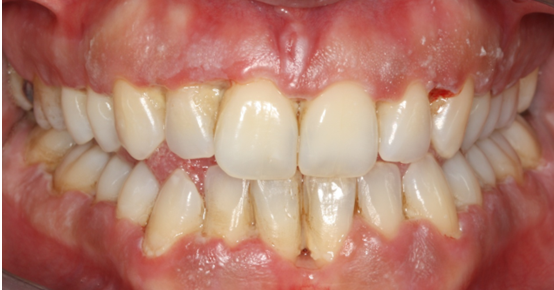

13. Θεραπεία χρόνιας περιοδοντίτιδας

Ασθενής ετών 50 προσήλθε στο ιατρείο με κύρια ενόχληση την αιμορραγία των ούλων και τη μετακίνηση των δοντιών. Οι περιοδοντικοί ιστοί ήταν ρόδινοι και εντοπισμένα ερυθροί, ενώ οι μεσοδόντιες θηλές διογκωμένες. Πολλά δόντια εμφάνιζαν υφιζήσεις, ενώ χαρακτηριστική ήταν η υπερέκφυση και απόκλιση του πλαγίου τομέα άνω αριστερά.

Παράλληλα με την περιοδοντική θεραπεία έγινε η αφαίρεση των παλαιών προσθετικών εργασιών και τοποθέτηση νέων μεταβατικών (προσωρινών) αποκαταστάσεων. Μετά τη μη χειρουργική θεραπεία παρατηρείται απουσία φλεγμονής.

ΑΡΧΙΚΗ ΚΛΙΝΙΚΗ ΕΙΚΟΝΑ

ΤΕΛΙΚΗ ΚΑΤΑΣΤΑΣΗ